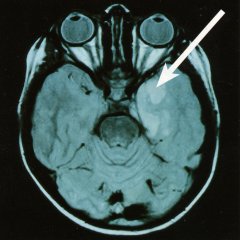

The MRT image shows a benign brain tumour which stands out in a lighter colour against the healthy tissue (see arrow). Such tumours can cause epileptic seizures. Most patients become seizure free after the tumour has been removed. |